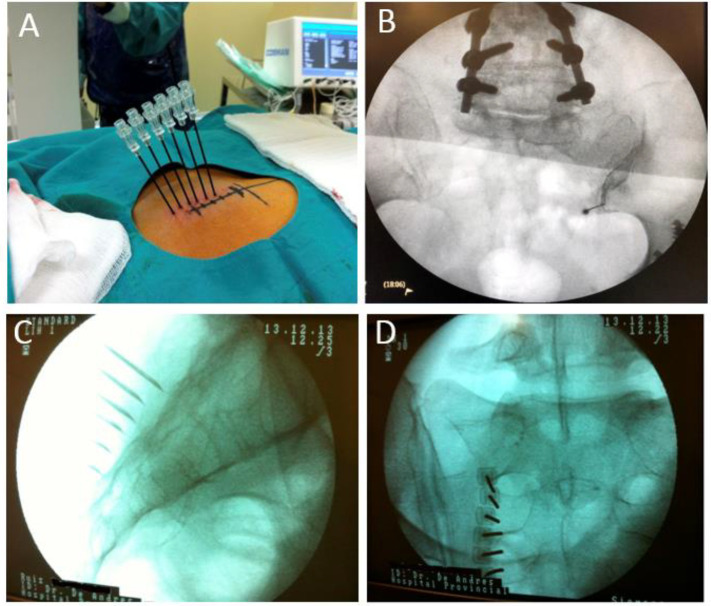

Palisade Technique (alternative):

• Six or more needles placed no more than 1 cm apart along a straight line 8-10 mm lateral to the arcuate line

• Spans from just above the S1 foramen to the mid-lower margin of S3 (or S4)

• Creates a continuous strip of anesthesia covering all pertinent lateral branches